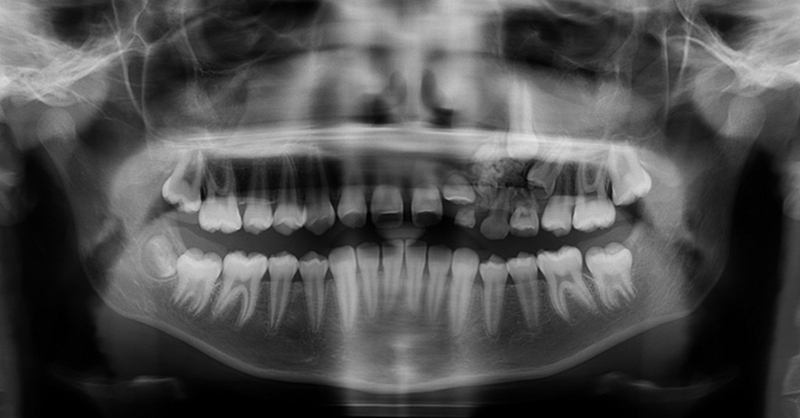

Hình ảnh X-quang của u răng phức hợp phụ thuộc vào giai đoạn phát triển và mức độ canxi hóa của chúng. Giai đoạn đầu tiên được đặc trưng bởi độ thấu quang do thiếu vôi hóa mô răng, tiếp theo là giai đoạn trung gian được đặc trưng bởi sự vôi hóa một phần của mô tạo men với hình ảnh cản quang điển hình. Ở giai đoạn thứ ba, tổn thương thường xuất hiện cản quang với các khối mô cứng răng vô định hình được bao quanh bởi một vùng thấu quang mỏng tương ứng về mặt mô học với bao liên kết.

U răng là các tổn thương mô thừa bao gồm men răng, ngà răng và tủy trưởng thành, có thể là u răng phức hợp hay đa hợp tùy thuộc vào mức độ biệt hóa hình thái hoặc sự giống nhau của chúng với răng bình thường. U răng thường không ác tính, phát triển chậm và thường được chẩn đoán vô tình khi chụp phim X quang. Chẩn đoán được xác định sau khi phẫu thuật cắt bỏ và phân tích mô bệnh học của tổn thương.

U răng thường không có triệu chứng và được phát hiện tình cờ trên phim chụp X-quang. Dấu hiệu lâm sàng của u răng có thể bao gồm không thay răng sữa, răng vĩnh viễn không mọc, đau, giãn xương răng và dịch chuyển răng. Các triệu chứng khác có thể xuất hiện bao gồm khó nuốt, tê ở môi dưới, đau đầu vùng trán và sưng ở bên bị ảnh hưởng.